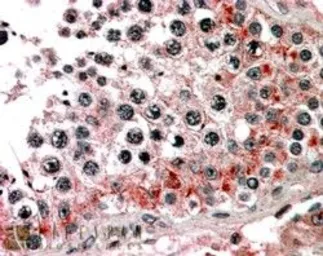

ABCB9 antibody, C-term

Cat. No. GTX89769

ApplicationsIHC-P

ReactivityHuman